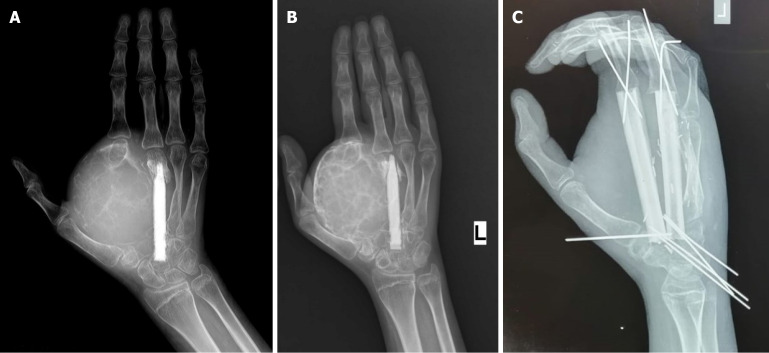

Results: As of December 2024, 43 patients have been reported in the literature who received DT for locally advanced/unresectable ABCs. There were 27 males and 16 females with a mean age of 15.8 years. At a median follow-up time of 15.5 months, there were 10 confirmed and two pathologically unconfirmed relapses after denosumab discontinuation. All 10 relapses occurred in patients in Group 1 at a median time of 13.5 months. Among patients in Group 2, with a median follow-up time of 12.5 months after completion of therapy, no local relapses were observed. The difference between local recurrence rates (32% vs 0%) is statistically significant (P value = 0.02). Kaplan-Meier estimates show the same trend with marginal statistical significance (P value = 0.085). Here we put forward a novel treatment algorithm.